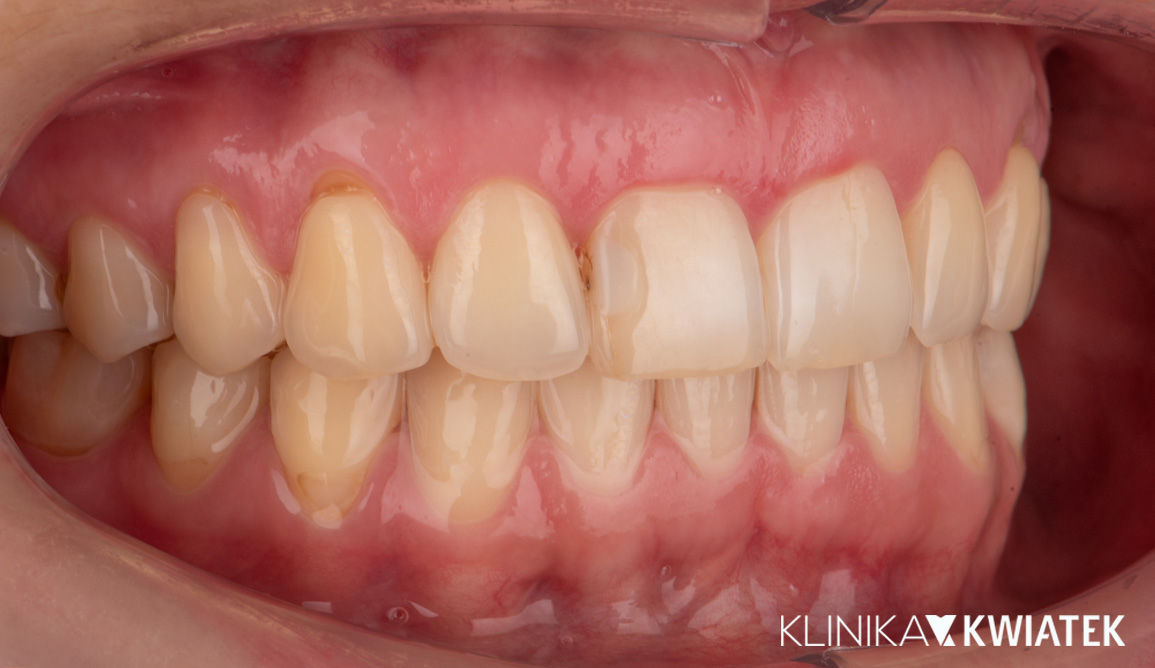

Kompleksowa transformacja uśmiechu po leczeniu ortodontycznym

Pacjentka zgłosiła się do kliniki po zakończeniu leczenia ortodontycznego nakładkami w innym gabinecie, w celu odbudowy brakującego zęba trzonowego. Po szczegółowej diagnostyce zaplanowano leczenie implantologiczne, protetyczne oraz periodontologiczne. Dzięki precyzyjnej pracy zespołu specjalistów uzyskano pełną odbudowę estetyki i funkcji – naturalny, harmonijny uśmiech oraz zdrowe, stabilne przyzębie.